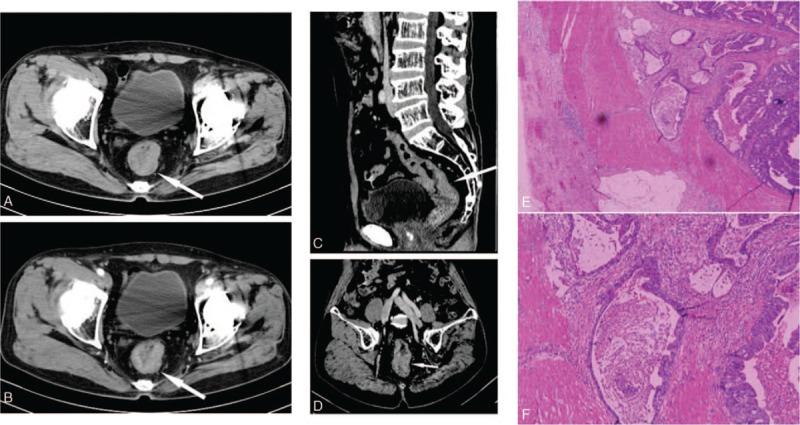

This study aims to evaluate the diagnostic accuracy and clinical application value of multi-slice spiral CT (MSCT) enhanced scans combined with multiplanar reformations (MPRs) images compared with postoperative pathological results in preoperative T staging of rectal cancer.One hundred sixty-eight consecutive patients with rectal cancer were admitted in our hospital between January 2013 and October 2018. Conventional MSCT plain scans, multi-phase dynamic contrast-enhanced scans, and MPRs were performed in all patients before surgical operation. The preoperative T staging of the rectal cancer lesions was evaluated using MSCT enhanced scans combined with MPRs, which was verified by postoperative pathological results. The diagnostic accuracy of MSCT enhanced scans combined with MPRs in evaluating T staging of the rectal cancer lesions were analyzed by χ test and Kappa test.Compared with postoperative pathology, T staging using MSCT enhanced scans combined with MPRs had overall accuracy of 85.7%. Consistency between MSCT enhanced scans combined with MPRs and postoperative pathological staging was effective for T staging (Kappa = 0.658, χ = 4.200, P = .122).Conventional MSCT enhanced scans combined with MPRs are simple and feasible. It is consistent with the pathological diagnosis of evaluating T staging in the rectal cancer lesions. It can provide reliable imaging evidence for the preoperative evaluation of primary rectal cancer, especially in patients with magnetic resonance imaging (MRI) contraindications, or in grass-roots hospitals due to lack of MRI equipment.

本研究旨在评估多层螺旋CT(MSCT)增强扫描联合多平面重建(MPR)图像在直肠癌术前T分期中与术后病理结果相比的诊断准确性及临床应用价值。2013年1月至2018年10月期间,我院连续收治168例直肠癌患者。所有患者在手术前均进行了常规MSCT平扫、多期动态对比增强扫描及MPR。采用MSCT增强扫描联合MPR对直肠癌病变进行术前T分期评估,并与术后病理结果进行对照验证。通过χ检验和Kappa检验分析MSCT增强扫描联合MPR在评估直肠癌病变T分期中的诊断准确性。与术后病理结果相比,MSCT增强扫描联合MPR进行T分期的总体准确率为85.7%。MSCT增强扫描联合MPR与术后病理分期的一致性在T分期方面有效(Kappa=0.658,χ=4.200,P=0.122)。常规MSCT增强扫描联合MPR简单可行,在评估直肠癌病变T分期方面与病理诊断结果一致,可为原发性直肠癌的术前评估提供可靠的影像学依据,尤其适用于有磁共振成像(MRI)禁忌证的患者或因缺乏MRI设备的基层医院。